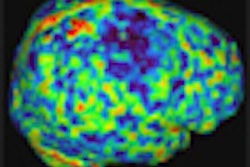

Large variations in dose among the different centers validated the second objective of the survey, which was to determine the need to initiate a set of standard DRL values for brain, chest, and abdomen CT exams based on age/weight of patients.

| Variations of displayed volume CT dose index by procedure type and patient age

|